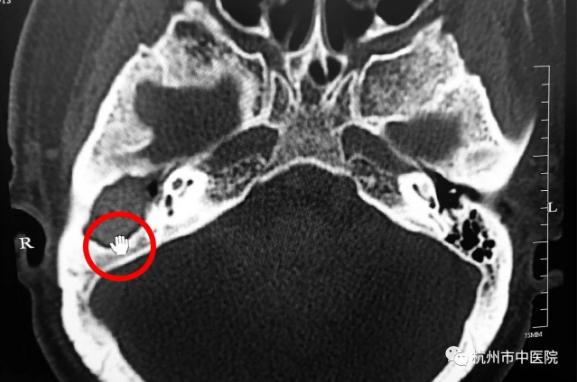

ct片

“你先别哭呀,胆脂瘤并不是真正的肿瘤,可以手术除去的。”苏立众主任忙安慰泪眼婆娑的小林别紧张,并简单介绍此少见疾病的来龙去脉,然后开具了颞骨CT检查。

不出所料,颞骨CT检查显示小林左侧外耳道胆脂瘤,已挤压破坏左侧听骨链,且与左侧颈静脉及面神经管等重要结构关系密切,所以小林疼痛症状明显,左耳听力已有明显的下降。一切明了,小林如释重负。